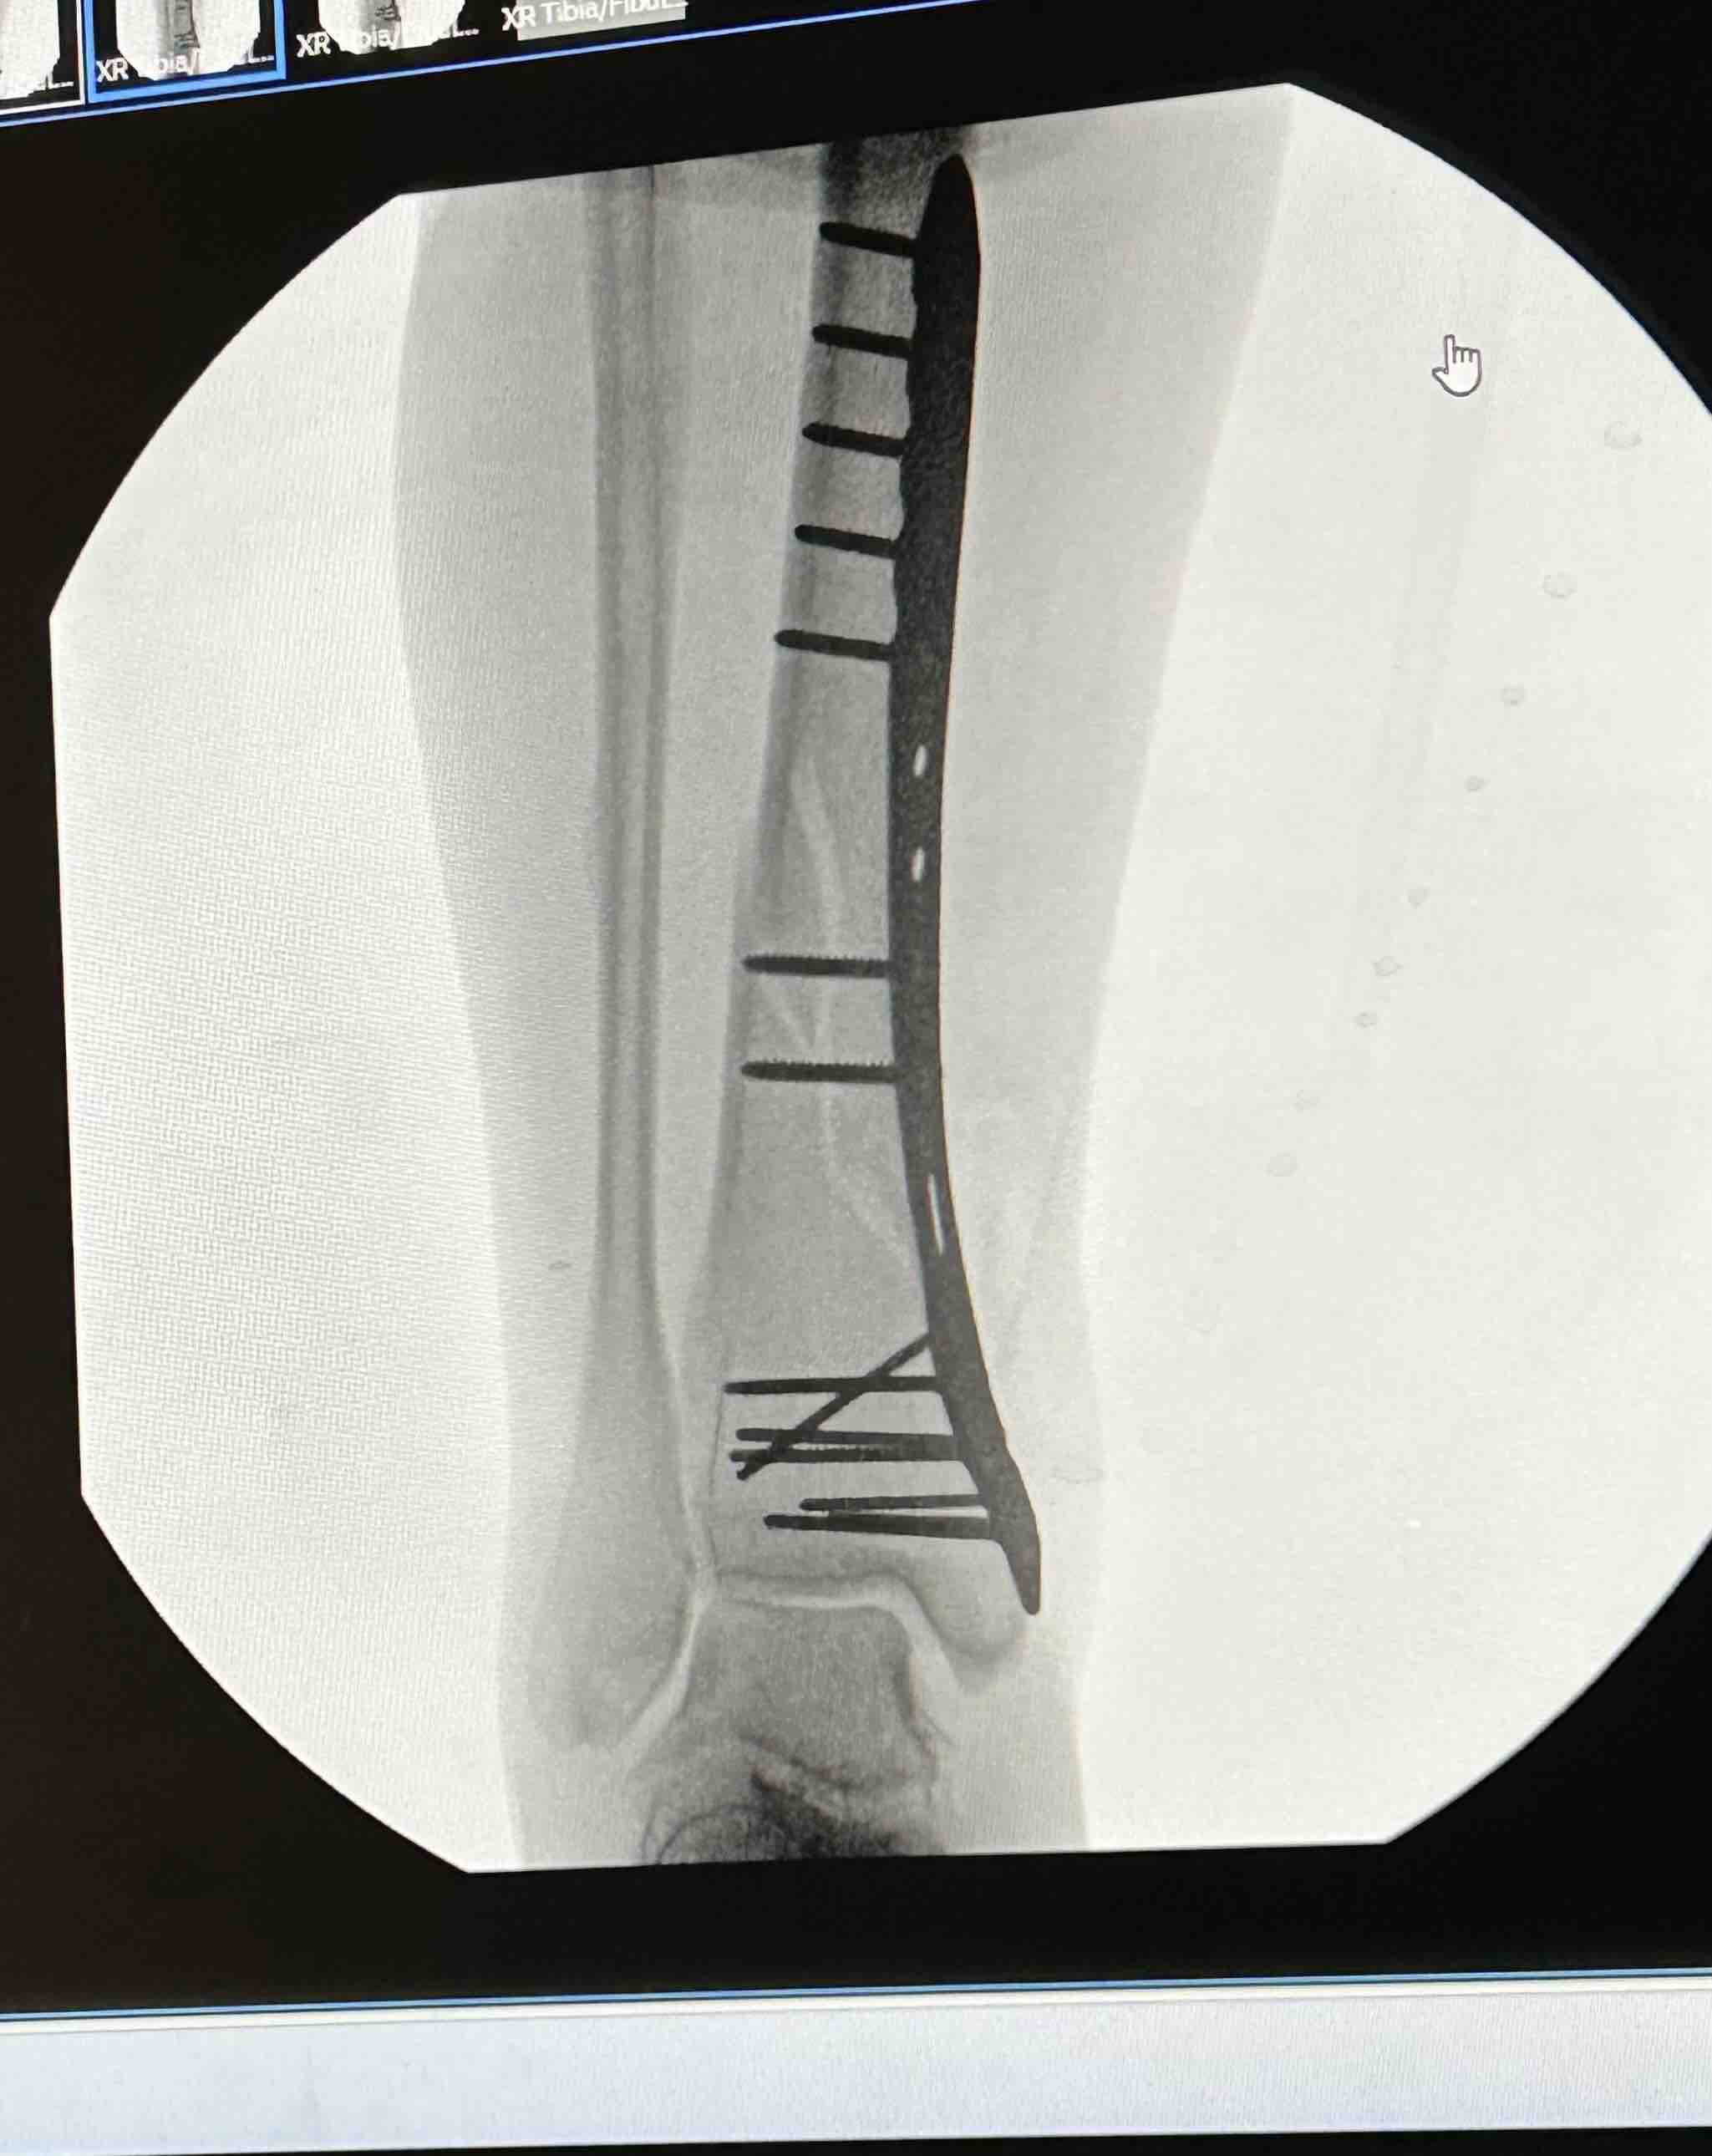

Hello my name is Rachel and I’m usually a pretty active and healthy girl. I was taken to the Murray Hospital February 15th and discharged on the 24th due to severe pancreatitis and pneumonia. I was home only a couple days and still felt very weak and tired. I attempted to go into my bathroom and somehow lost my footing and my whole body landed on my right leg and broke my right tibia and fibula (8.0 cm severely comminuted fracture of the proximal fibular shaft and 10.2 cm spiral fracture distal tibial shaft). 2 very bad fractures . It was the worst pain I’ve ever experienced! It took me 30 mins to crawl about 30 feet to my bed where my phone was to call 911 for help. The paramedics wouldn’t let me look at my leg and kept telling me to try to just lay down and relax, which was extremely hard to do. I was told my leg looked crooked and my foot was turned all the way to the side. With the help of the fire department, I was able to make it down my steps and to the ER. I had 2 doctors come in while in the ER and reset it the best they could until I could have surgery. Was supposed to be the next day but a special plate and screws had to be sent to the hospital so Sunday morning at 8am, an hour long surgery took almost 3. I now have a 9 inch place and 13 screws in my leg on one of the fractures. Depending on how the other fracture looks when I see my Ortho for follow up, I may need another surgery to put a plate on it as well. I am non weight bearing for 6-8 weeks and won’t be able to drive for no earlier than 6 months. Full recovery is a year or more. Since I am not currently working, I have applied and talked to many people about getting some sort of disability to help me keep my apartment but not getting a lot of good answers so far. I have even had my doctors send in letters stating my condition and how severe it is but it’s not getting anywhere. If anyone could find it in their heart to help me stay above water, I would greatly appreciate it!! Even a couple dollars goes a long way! All money will go to medical expenses including physical therapy, doctor appointments, medicine and the rental of medical equipment I need to get around. I didn’t want to have to make this but I’m in a rough place right now and could really use the help. Any help is appreciated. Thank you and God Bless!